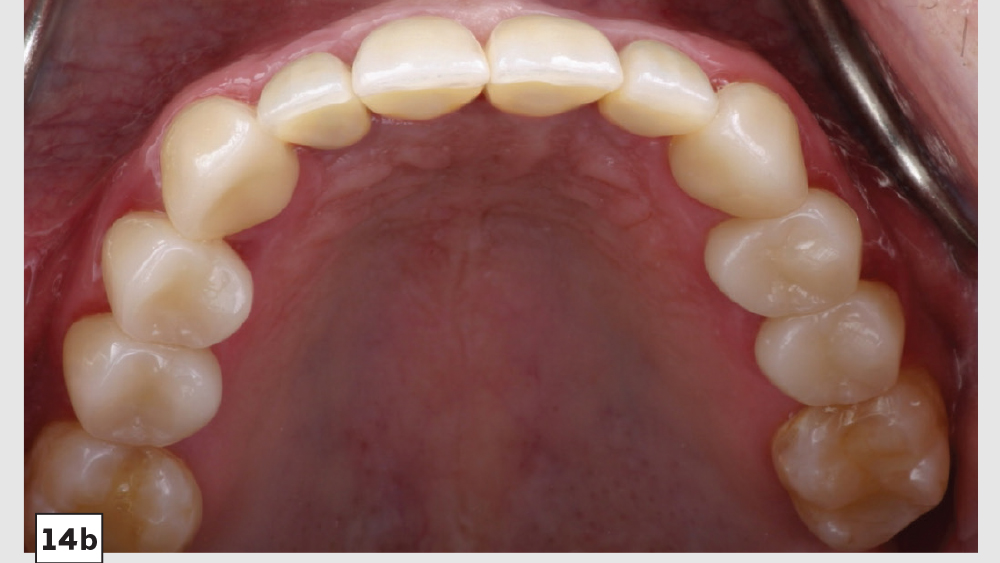

This patient came to me with four missing anterior teeth in positions #7–10. He had been missing these teeth for some time and was wearing a temporary denture to address the cosmetic issue this created. When he came to my practice, he was in a financial position to solve the problem permanently with implant restorations. Based upon the anterior space available and the fact that the patient’s surrounding tissue was in good health, I chose to move forward with Hahn™ Tapered Implants and BruxZir® Esthetic restorations.

There’s nothing more rewarding than when patients return to your office for additional dentistry because they were so thrilled with the results of the previous procedure you performed for them. This particular patient followed through with the additional treatment I had previously recommended.